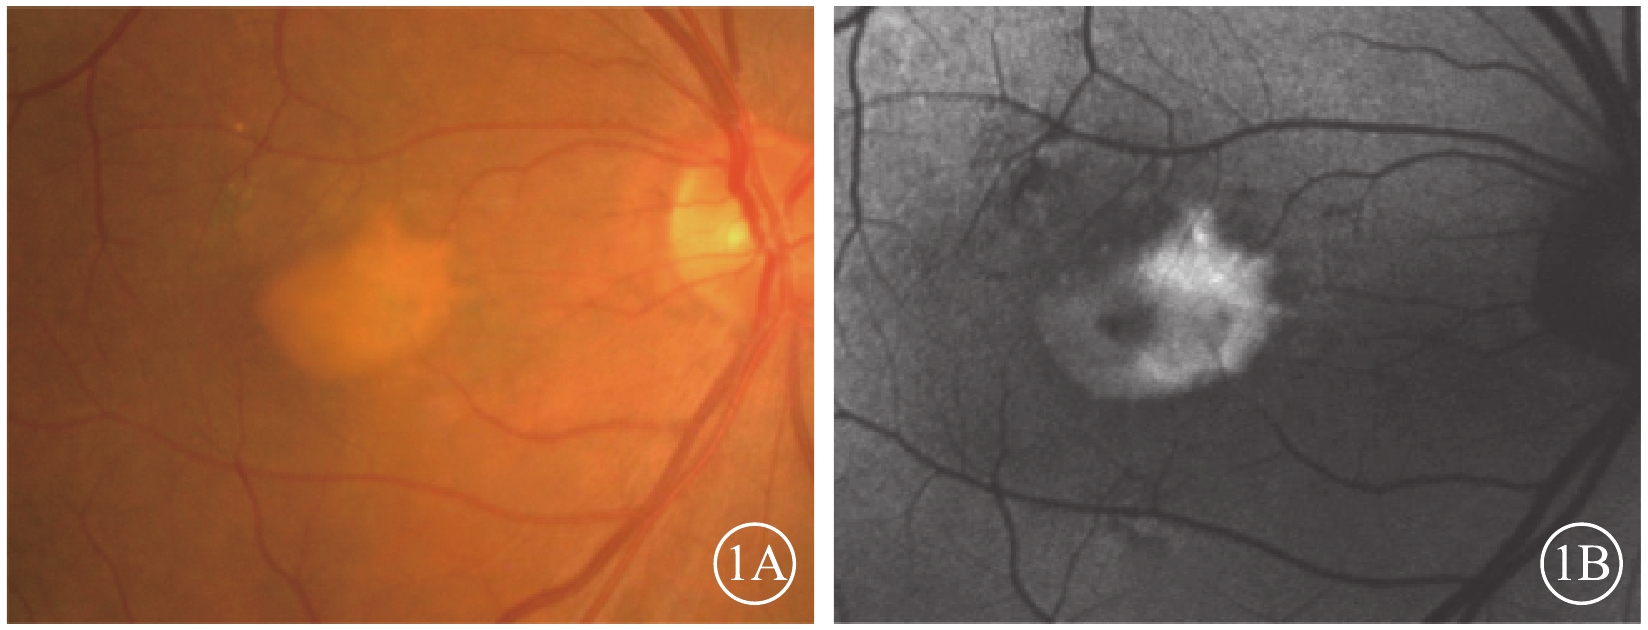

眼底彩色照相檢查發現,所有患眼黃斑區視網膜下可見一邊界清晰的黃白色病灶(圖1A),黃斑區終末血管爬行于病灶之上。黃白色病灶密度并不完全一致,部分區域病變較為濃密,部分則較為稀薄。病灶內部及周圍未見出血、滲出。病灶周圍可見小片狀色素脫失(圖1A)。其余部分視網膜、視神經、血管均未見異常。

FAF檢查發現,所有患眼均可見與彩色眼底像中病灶一致的強自身熒光。病灶內自身熒光強度不一(圖1B),彩色眼底像中較為稀薄的區域呈相對弱自身熒光,較為濃密的區域呈強自身熒光。與彩色眼底像對應的小片狀色素脫失區域可見弱自身熒光(圖1B)。

圖1

AOFVD患眼彩色眼底、FAF像。1A. 彩色眼底像,黃斑區視網膜下可見邊界清晰的黃白色病灶,病灶周圍可見小片狀色素脫失;1B. FAF像。與彩色眼底像對應的病灶處可見強自身熒光,病灶內自身熒光強度不一;與彩色眼底像對應的小片狀色素脫失區域可見弱自身熒光

圖1

AOFVD患眼彩色眼底、FAF像。1A. 彩色眼底像,黃斑區視網膜下可見邊界清晰的黃白色病灶,病灶周圍可見小片狀色素脫失;1B. FAF像。與彩色眼底像對應的病灶處可見強自身熒光,病灶內自身熒光強度不一;與彩色眼底像對應的小片狀色素脫失區域可見弱自身熒光

眼底彩色照相檢查發現,所有患眼黃斑區視網膜下可見一邊界清晰的黃白色病灶(圖1A),黃斑區終末血管爬行于病灶之上。黃白色病灶密度并不完全一致,部分區域病變較為濃密,部分則較為稀薄。病灶內部及周圍未見出血、滲出。病灶周圍可見小片狀色素脫失(圖1A)。其余部分視網膜、視神經、血管均未見異常。

FAF檢查發現,所有患眼均可見與彩色眼底像中病灶一致的強自身熒光。病灶內自身熒光強度不一(圖1B),彩色眼底像中較為稀薄的區域呈相對弱自身熒光,較為濃密的區域呈強自身熒光。與彩色眼底像對應的小片狀色素脫失區域可見弱自身熒光(圖1B)。

圖1

AOFVD患眼彩色眼底、FAF像。1A. 彩色眼底像,黃斑區視網膜下可見邊界清晰的黃白色病灶,病灶周圍可見小片狀色素脫失;1B. FAF像。與彩色眼底像對應的病灶處可見強自身熒光,病灶內自身熒光強度不一;與彩色眼底像對應的小片狀色素脫失區域可見弱自身熒光

圖1

AOFVD患眼彩色眼底、FAF像。1A. 彩色眼底像,黃斑區視網膜下可見邊界清晰的黃白色病灶,病灶周圍可見小片狀色素脫失;1B. FAF像。與彩色眼底像對應的病灶處可見強自身熒光,病灶內自身熒光強度不一;與彩色眼底像對應的小片狀色素脫失區域可見弱自身熒光